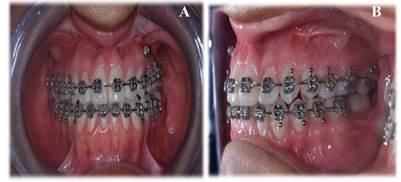

Se instaló aparatología fija prequirúrgica como parte del tratamiento ortodóntico preparatorio para la cirugía ortognática (Figura 4). Este paso es esencial para alinear y nivelar las arcadas dentarias, permitiendo que los dientes y las estructuras óseas estén en la posición óptima al momento de la intervención quirúrgica, lo que facilita una correcta oclusión postoperatoria.

Figura 4 Fotografías intraorales post colocación de tratamiento ortodónticos A: Oclusión vista frontal B: Oclusión vista lateral izquierda.